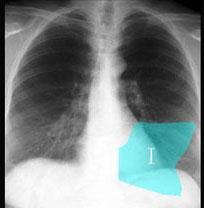

在图所示正常胸部X线影像图像上,该英文字母所代表的肺段为 ( )A、后基底段B、背段C、前基底段D、外基底段E、内基底段

问题 在图所示正常胸部X线影像图像上,该英文字母所代表的肺段为 ( )

选项 A、后基底段 B、背段 C、前基底段 D、外基底段 E、内基底段

答案 A